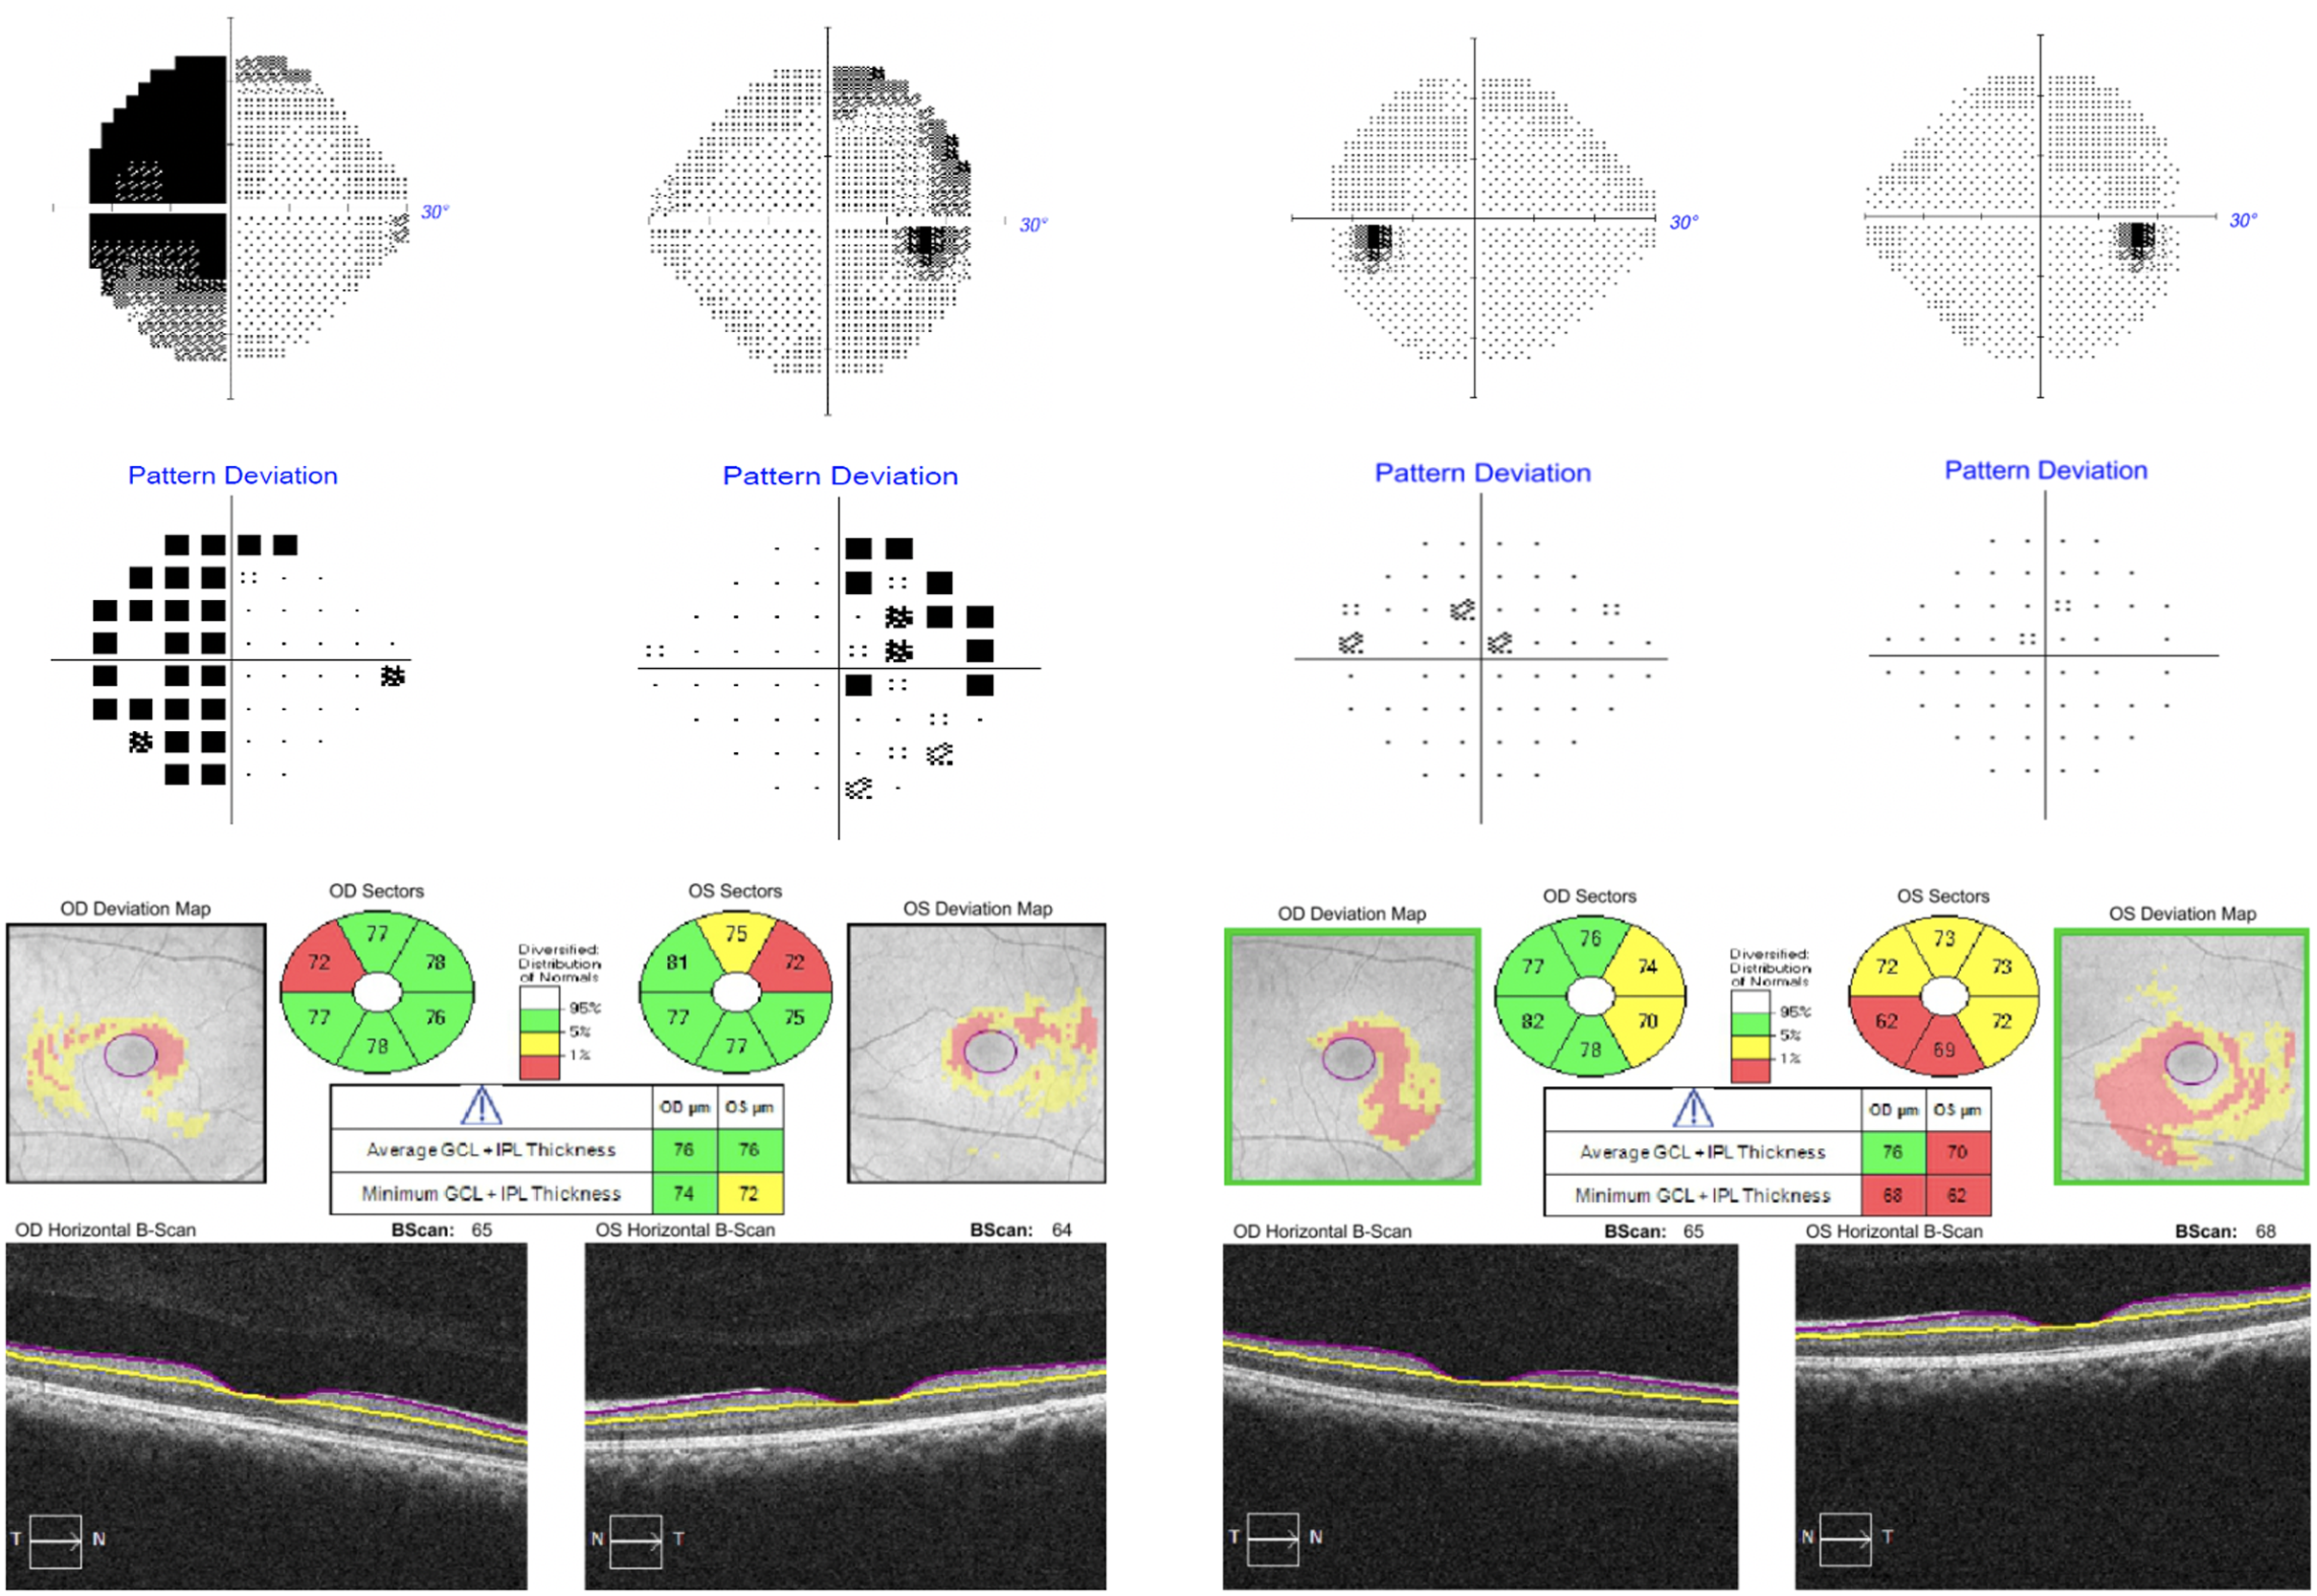

A 27-year-old woman was referred to neuro-ophthalmology for a 2-month history of left greater than right vision loss. She was 17 weeks pregnant (G5P1), but otherwise healthy and on no medications. Initial examination revealed a visual acuity of 20/20 OD and 20/30-2 OS. Humphrey 24-2 SITA-Fast visual fields (HVF) showed a left greater than right bitemporal hemianopia (Figure 1A). Optical coherence tomography (OCT) of the macular ganglion cell-inner plexiform layer (GCIPL) showed very subtle binasal thinning (Figure 1C). An MRI of the sella with contrast was performed and showed a “snowman-shaped” intrasellar and suprasellar, 24 × 20 × 17 mm mass compressing the optic chiasm (Figure 2A). The mass had cystic changes at the suprasellar component, which demonstrated intrinsic T1 hyperintensity within the cyst. The patient had normal endocrinological evaluation in the context of her pregnancy, which included normal adrenocorticotropic hormone (5.4 pmol/L), growth hormone (2.3 µg/L), prolactin (91.1 µg/L), and thyroid-stimulating hormone (1.89 µIU/mL). A neurosurgical consultation recommended surgical resection with the goal of improving and preserving her vision. The patient declined surgical intervention and decided to reconsider after delivery. Her visual field remained essentially stable throughout pregnancy. She delivered her baby via C-section after which she decided to reconsider surgery. However, she noticed a significant improvement in her visual field 5-month post-partum. She continued to notice a gradual improvement over the next several months and at the 15-month post-partum follow-up, her visual acuity was 20/20 in both eyes, HVF was normal (Figure 1B) and OCT GCIPL showed binasal atrophy (Figure 1D). A repeat MRI sella showed stable size of the intrasellar and suprasellar mass with interval decrease in T1 signal of the suprasellar cystic component (Figure 2B). There was stable mass effect on the optic chiasm and pre-chiasmatic optic nerves with the interval development of high T2-signal in the optic nerves.

Figure 1: Humphrey 24-2 SITA-Fast visual fields at presentation (A, top left) and final follow-up (B, top right). OCT macular ganglion cell analysis at presentation (C, bottom left) and final follow-up (D, bottom right).